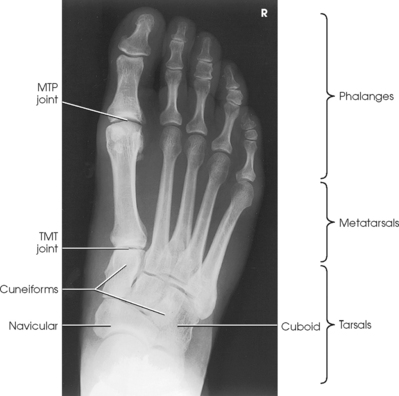

The foot consists of 26 bones (Figs. 6-1 and 6-2):

The bones of the foot are similar to the bones of the hand. Structural differences permit walking and support of the body’s weight. For descriptive purposes, the foot is sometimes divided into the forefoot, midfoot, and hindfoot. The forefoot includes the metatarsals and toes. The midfoot includes five tarsals—the cuneiforms, navicular, and cuboid bones. The hindfoot includes the talus and calcaneus. The bones of the foot are shaped and joined together to form a series of longitudinal and transverse arches. The longitudinal arch functions as a shock absorber to distribute the weight of the body in all directions, which permits smooth walking (see Fig. 6-2). The transverse arch runs from side to side and assists in supporting the longitudinal arch. The superior surface of the foot is termed the dorsum or dorsal surface, and the inferior, or posterior, aspect of the foot is termed the plantar surface.

The five metatarsals are numbered one to five beginning at the medial or great toe side of the foot. The metatarsals consist of a body and two articular ends. The expanded proximal end is called the base, and the small, rounded distal end is termed the head. The five heads form the “ball” of the foot. The first metatarsal is the shortest and thickest. The second metatarsal is the longest. The base of the fifth metatarsal contains a prominent tuberosity, which is a common site of fractures.

Beginning at the medial side of the foot, the cuneiforms are described as medial, intermediate, and lateral.

The cuboid bone lies on the lateral side of the foot between the calcaneus and the fourth and fifth metatarsals (see Fig. 6-1). The navicular bone lies on the medial side of the foot between the talus and the three cuneiforms. The cuneiforms lie at the central and medial aspect of the foot between the navicular bone and the first, second, and third metatarsals. The medial cuneiform is the largest of the three cuneiform bones, and the intermediate cuneiform is the smallest.

The interphalangeal (IP) articulations, between the phalanges, are synovial hinges that allow only flexion and extension. The joints between the distal and middle phalanges are the distal interphalangeal (DIP) joints. Articulations between the middle and proximal phalanges are the proximal interphalangeal (PIP) joints. With only two phalanges in the great toe, the joint is known simply as the IP joint.

The distal heads of the metatarsals articulate with the proximal ends of the phalanges at the metatarsophalangeal (MTP) articulations to form synovial ellipsoidal joints, which have movements of flexion, extension, and slight adduction and abduction. The proximal bases of the metatarsals articulate with one another (intermetatarsal articulations) and with the tarsals (tarsometatarsal [TMT] articulations) to form synovial gliding joints, which permit flexion, extension, adduction, and abduction movements.